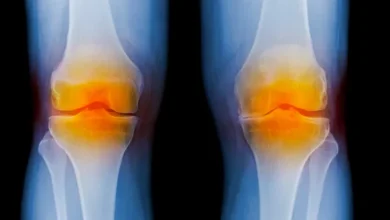

يصيب 46% أكثرهم من النساء..كيف نتجنب الخشونة ونمنع آلام الركبة؟

أصبحت الإصابة بالخشونة والآلام المزمنة في الركبة آفة تهدد نحو نصف عدد البشر (حسب الإحصائيات) خاصة مع تقدم العمر،…